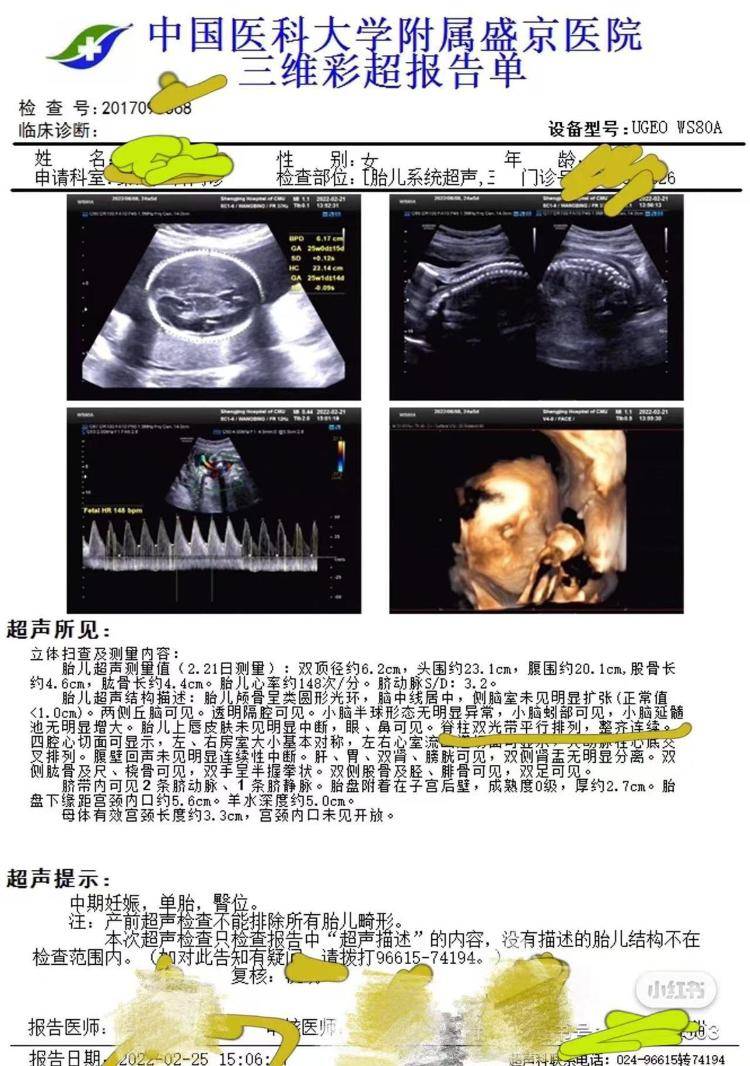

3月11日,高女士告诉极目新闻记者,2021年10月,她到盛京医院做了第一次产检并预约了后续的检查,2022年2月25日,她在盛京医院做了包括胎儿系统超声在内的大排畸检查,检查结果显示胎儿“脊柱双光带平行排列,整齐连续”,2022年6月15日,女儿出生。同年12月,女儿在核磁检查时被确诊脂肪脊髓脊膜膨出和椎管内脂肪瘤,即“脊柱裂”,“脊柱裂意味着女儿后期需要多次手术治疗,否则会足踝畸形、大小便失禁,严重的话甚至会导致下半身瘫痪。”

产前彩超显示胎儿脊柱正常(受访者供图)

高女士表示,沈阳市卫健委的调查结果仅回应了她的部分诉求,她自始至终还是没有看到盛京医院提供的彩超原始图像,“大排畸的彩超会产生多张切面图像,但医院只提供了三维彩超报告单,原始图像却没有。”2025年4月,她再次向沈阳市卫健委申诉,要求调查处理盛京医院,并请其敦促院方提供彩超原始图像,沈阳市卫健委回复称让盛京医院自行处理,但盛京医院明确表示了拒绝。据2025年6月24日盛京医院的回复内容显示,现行法律法规并未强制规定医疗机构必须向患者提供此类病案范畴内的电子影像数据复制服务。医院拒绝向患者提供孕期彩超切面影像数据的复制服务,这一做法并非出于欺瞒患者的目的,而是基于以下考虑:一方面,是为了避免患者对专业性较强的影像数据产生理解误区,从而引发不必要的担忧和误解;另一方面,也是为了促进医学事业的发展,以及保护患者和医师双方的权益。